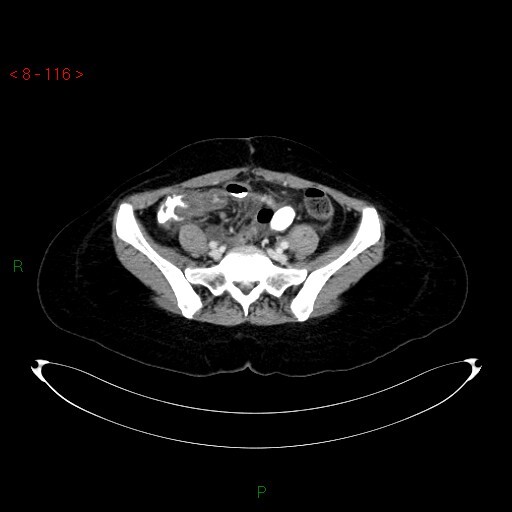

Paciente no PO de cirurgia ortopédica. HD?

Pseudobstrução Colônica (Síndrome de Ogilvie).

Distensão aguda do cólon por redução da atividade parassimpática do intestino grosso, leva à perda do peristaltismo colônico, frequentemente pós-operatório.

Mais comum em homens > 60 anos.

Ocorre em pacientes graves ou hospitalizados.